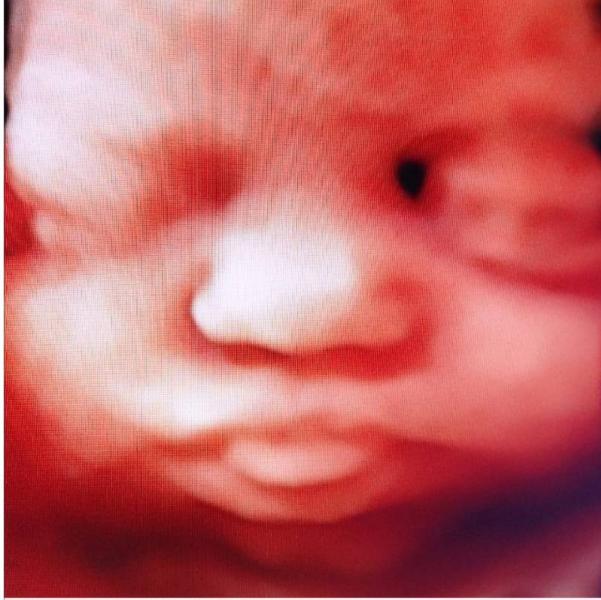

Я работаю на узи с 2007 г, т.е. уже 18 лет. 3д делаю с 2015 г, т.е. 10 лет.

Сейчас покажу фотки с 2015 ,2016 ,2018 гг.

И они нисколечко не уступают по красоте и качеству сделанным сегодня или вчера .

Если не нравится, проходите мимо. Мне очень нравится, поэтому делюсь . Это самое милое и очаровательное, что есть в этом мире . 😍